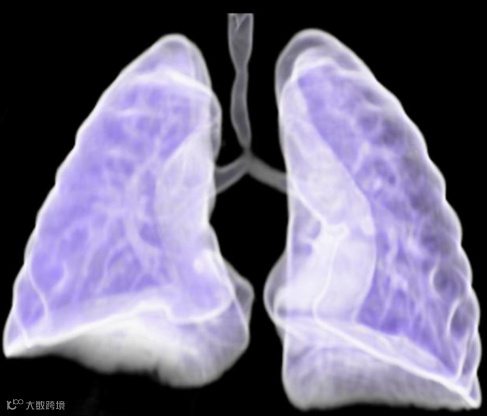

患儿,女,3月龄,既往肺动脉吊带修复术。

3D体积渲染显示远端气管存在短段狭窄。主支气管近乎水平(隆突呈倒T形)。

CT轴位显示气管远端呈僵硬“O”形环状的气管,提示存在完整的气管环,这通常与肺动脉吊带相关。